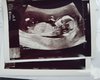

ale to podobna cena do lutinisa w Warszawie.No i pieknie czyli jefnak lewy test byl [emoji256][emoji256][emoji173][emoji173]Tak. Jesuuu.

Jest pozytyw i to znowu 2-3 tyg. Jadę na bete dziś.